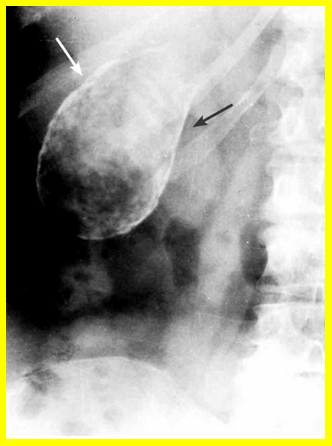

| תצלום 8.8: Percutanous trans-hepatic cholangiography (PTC) - תמונה שמאלית החץ מצביע על המחט והצנתר המוחדרים לדרכי המרה תמונה ימנית חץ מצביע על פגם בדרכי המרה G-כיס מרה 1- צינור מרה משותף. | |

- Percutaneus trans-hepatic cholangiography (PTC) (תצלום 8.8). בשיטה זו אפשר להדגים את דרכי המרה על-ידי ניקור מלעורי של הכבד. בניקור חודרים לכלי מרה בכבד ודרכו מזריקים חומר ניגוד לדרכי המרה ה"צובע" את העץ הביליארי. שיטה זו טובה בלוקים בערכי בילירובין גבוהים, שכן בהם אין לבצע את בדיקות הניגוד.

- בשיטה זו ניתן לבצע גם ניקוז קבוע של דרכי המרה על-ידי החדרת נקז לתוך דרכי המרה (PTD - percutaneus trans-hepatic drainage). התנאי להצלחת הבדיקה הוא דרכי מרה מורחבות, שאפשר לזהות בבדיקת אולטרה-סאונד של דרכי המרה (תמונה 9.8).

- בגישה זו אפשר גם לנקז את כיס המרה בחולים עם חסימות בצינור כיס המרה (איור 4.8) או לשלוף אבנים בעזרת מכשיר מיוחד ללכידת אבנים (Basket) (תצלום 10.8).